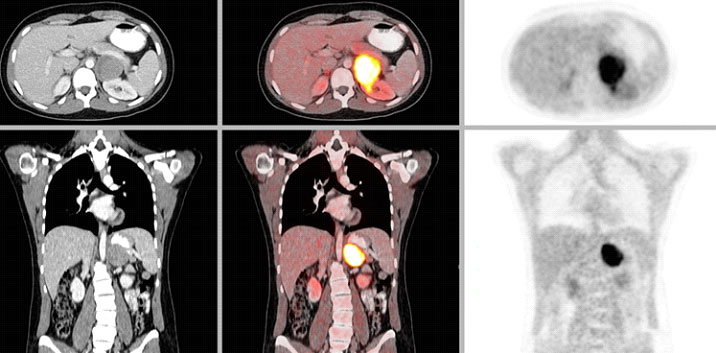

Pheochromocytoma Removed

Pheochromocytomas are treated with surgery to remove the adrenal gland that contains the tumor.

CT or MRI of the abdomen will almost always identify a pheochromocytoma. Additional specialized imaging such as MIBG (meta-iodobenzylguanidine) or Ga-68 Dotatate PET/CT scan can help to confirm a pheochromocytoma and identify multiple tumors or metastatic spread.